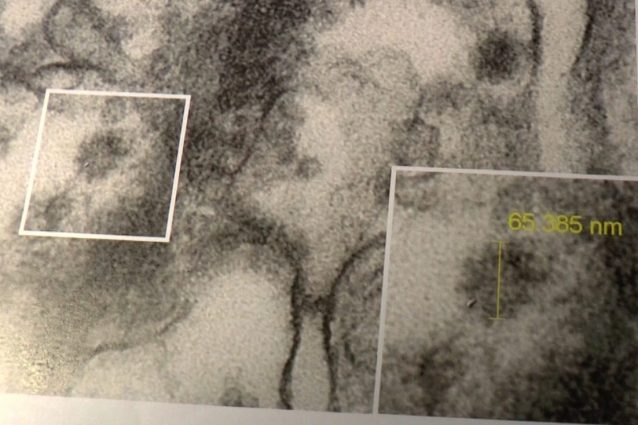

All'Istituto Mario Negri di Bergamo hanno individuato e "fotografato" il coronavirus all'interno di una cellula renale: "Averlo trovato è fondamentale per trovare la soluzione alla malattia", spiega in anteprima a Fanpage.it il direttore dell'Istituto, il professor Giuseppe Remuzzi. Per la prima volta in Europa è accertato il salto del virus oltre le barriere polmonari. Una scoperta fondamentale nello studio della cura perché i pazienti spesso muoiono per insufficienza renale, oltre che respiratoria. I ricercatori stanno testando farmaci già in vendita per malattie rare che avrebbero la capacità di interrompere la reazione a catena dell'organismo colpito dal Covid-19.